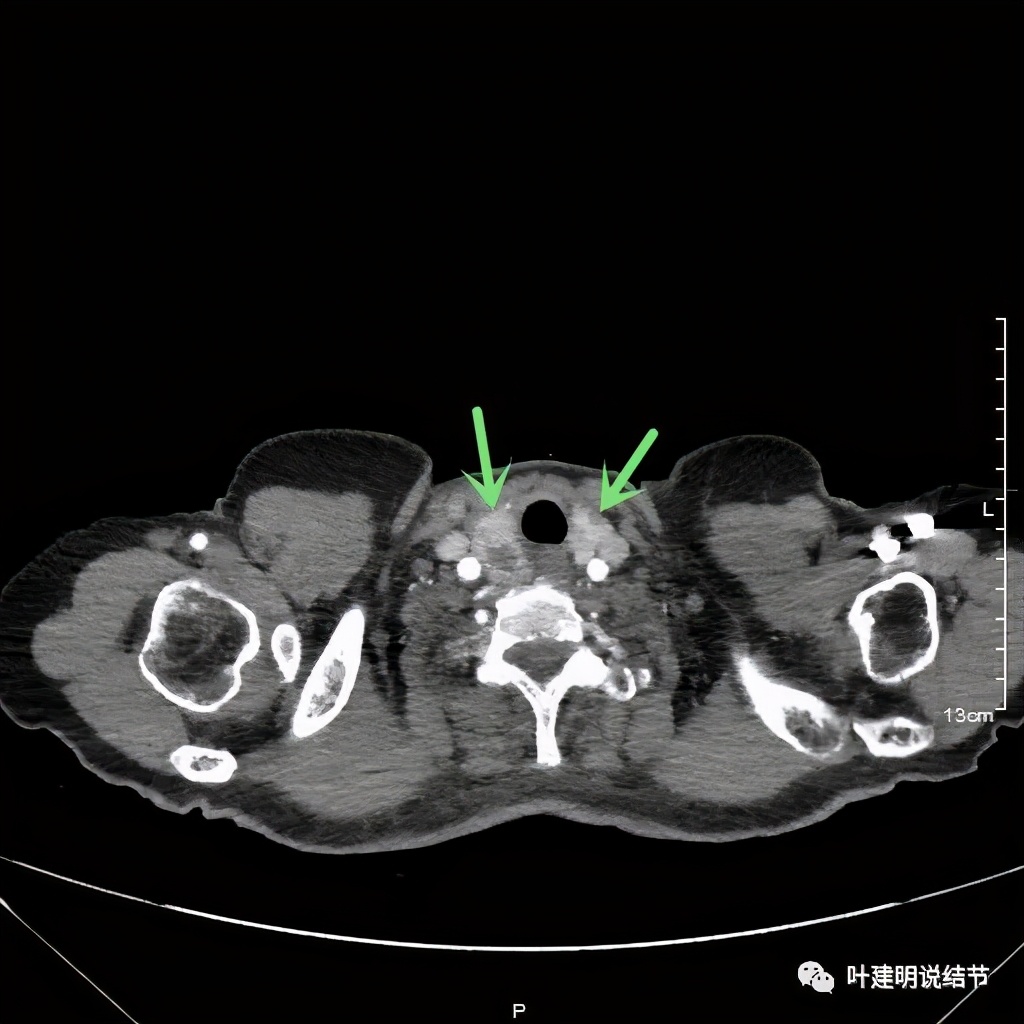

上图红色示肿瘤,黄色示气管,蓝色示上腔静脉,肿瘤已经快要消失了的层面,它距离隆突只有2点几厘米了,位置很低

我们由胸顶再往颈部一层一层看,结果真的肿瘤是与右侧甲状腺相连的!那么应该可能是甲状腺来源的纵隔肿瘤(胸内甲状腺肿瘤)。这样的话,其他的边缘界限清楚,这种密度以结节性甲状腺肿可能性大,不太像甲状腺恶性肿瘤。那么与气管间估计也是紧密靠着而已,不会是侵犯的。所以我们商量后就不穿刺,打算直接手术切除。术前做了冠脉CT,也有点问题,好在冠脉狭窄程度不重:

决定手术后,我们担心的是,肿瘤位置这么低,快到气管隆突部位了,能不能从颈部切口提上来?如果不能仅从颈部横切口完成手术,这么大年纪,再经胸做切口吃不吃得消?若与周围气管或无名静脉粘的紧,风险如何?术前我们与家属进行了充分沟通,也做好了术中翻身中转再经胸切口手术的准备。好在手术时发现肿瘤比较游离,钝性分离后能提到颈部掏出来,所以手术过程只有半小时光景就好了,只需颈部一个横切口、肿瘤大小约8-9厘米。这样的结果还是非常理想的,创伤也不大,恢复也会快,效果也好。术中病理示:结节性甲状腺肿。但是回想这个病例是有后怕的:如果我们医院扫描胸部时也到胸顶为止,甲状腺彩超双没有提示甲状腺结节与肿瘤的关系,临床医生可能容易疏忽掉,那么若穿刺了病理报结节性甲状腺肿,那也仍可能回头仍经颈部操作切除肿瘤。但临床有胸外科医生若一看是纵隔肿瘤,没有考虑穿刺活检或年纪不是这么大,直接经胸手术,那反而麻烦的多了,与甲状腺相连,经胸做不到颈部去,显露也不佳,可能够喝一壶的了!所以胸部CT扫描时往颈部扫一点,包括下颈部,见到甲状腺,则会减少这方面的疏漏。